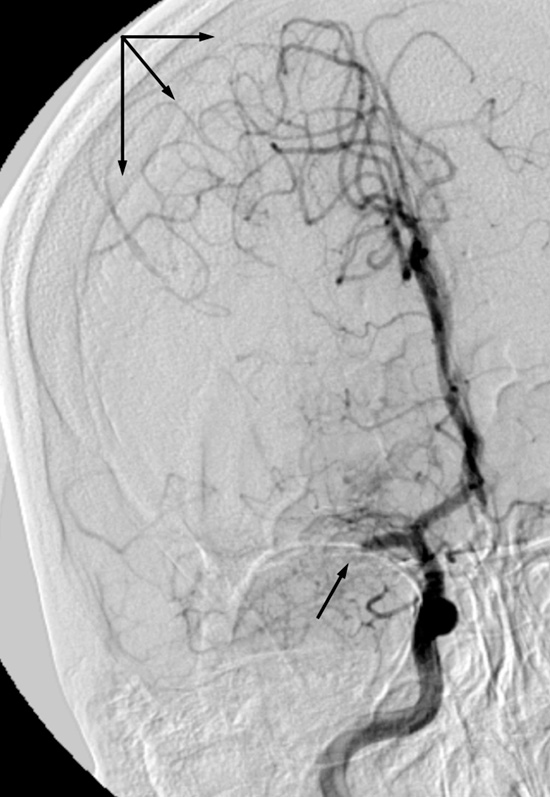

En kvinne tidlig i 30-årene ble innlagt i sykehus med akutte pareser i venstre kroppshalvdel. CT-angiografi viste okklusjon av høyre a. cerebri medias hovedstamme, og det ble startet intravenøs trombolytisk behandling. Under pågående infusjon ble hun sendt til Oslo universitetssykehus for endovaskulær behandling. Det ble utført vellykket embolektomi, med rekanalisering av arterien og rask klinisk bedring. Angiogrammene viser venstre fremre kretsløp før (venstre) og etter (høyre) prosedyren. National Institutes of Health Stroke Scale (NIHSS) ble skåret til 11 poeng ved innkomst (moderat alvorlig hjerneslag), 4 etter prosedyren (milde slagsymptomer) og 1 ved utskrivning (nær symptomfri). Av kjente vaskulære risikofaktorer bemerket vi røyking og bruk av p-piller.

Makroskopisk fremsto embolus uvanlig hard og lys i fargen. Bildet viser gramfarget snitt fra embolus med rikelig med grampositive kokker mot overflaten. Senere innleggelsesdagen ble pasienten febril, og det ble tatt blodkulturer, som ga oppvekst av streptokokker. Transøsofageal ekkokardiografi viste forandringer på mitralklaffen, med moderat insuffisiens, og det ble startet intravenøs behandling med antibiotika mot endokarditt. I ettertid fant vi at hun de siste månedene hadde oppsøkt lege flere ganger med influensaliknende feberepisoder.